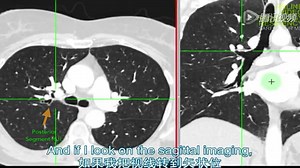

Bronchopulmonary Segments on CT Made Easy |Step-by-Step Radiology Guide

YouTube

radiology_defined

已浏览 218 次

2 周前

Chest CT- Bronchopulmonary Segments

2015年12月27日

qq.com

Lobar and Segmental Lung Anatomy on CT

已浏览 33.7万 次

2016年8月14日

Thoracic Radiology